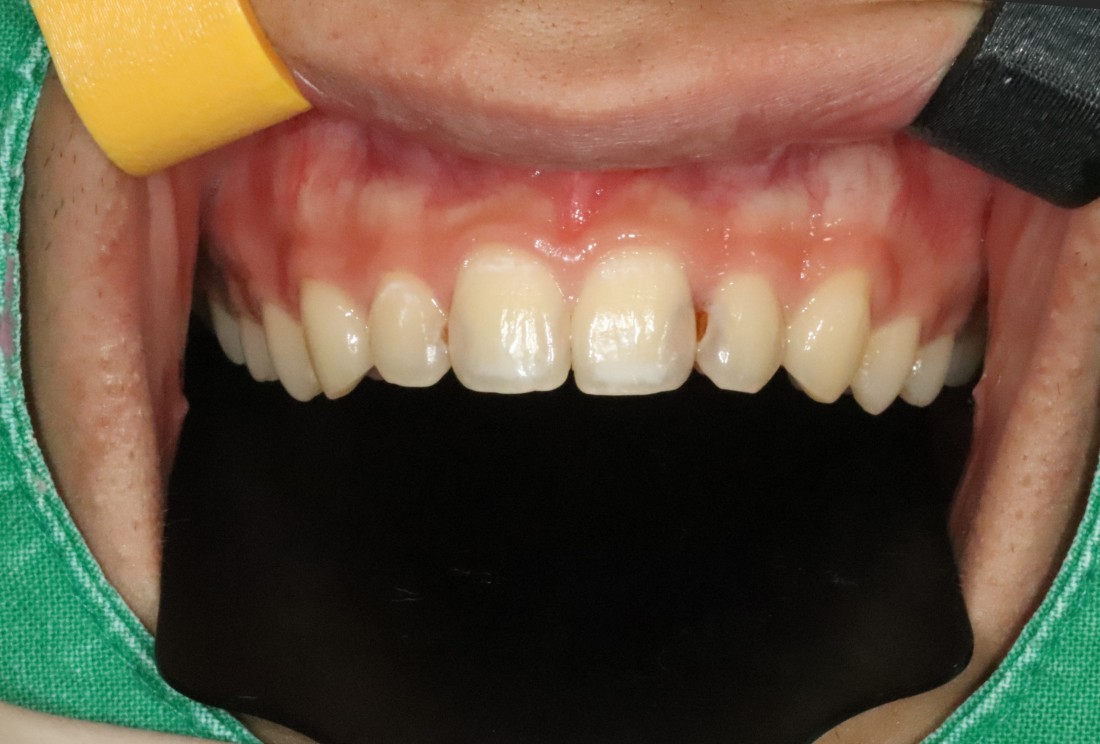

광주 라미네이트 치과에 방문해주신

40대 여성 고객님의 케이스입니다.

앞니 사이에 충치 치료로

검게 변색된 부분이

오랜시간 컴플렉스로 작용하셔서

환하게 웃지를 못했다고 하셨어요.

앞니를 자세히 보시면

색도 변색이 되었을 뿐만 아니라,

사이 충치로 인해 구멍이 생겨있어

세련된 첫인상에 부정적 영향을 끼치는데요.